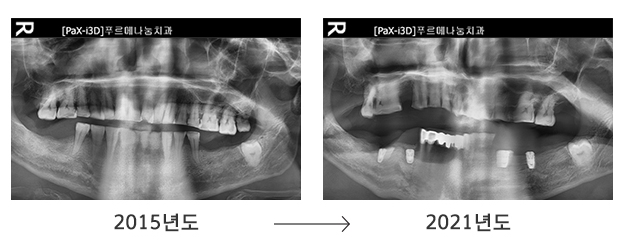

처음 푸르메치과의원을 방문했던 2013년, 2015년과 지금의 치아상태를 비교해보면 치아 보존 상태가 크게 악화된 것을 알 수 있습니다. 장애로 인해 신체의 불균형으로 치아가 비틀렸고 이갈이 습관으로 치아가 마모되고 망가진 것입니다. 비용 부담으로 미뤄왔던 치료는 결국 발치로 이어졌고 현재 남아있는 치아를 유지하기도 버거운 상황입니다.